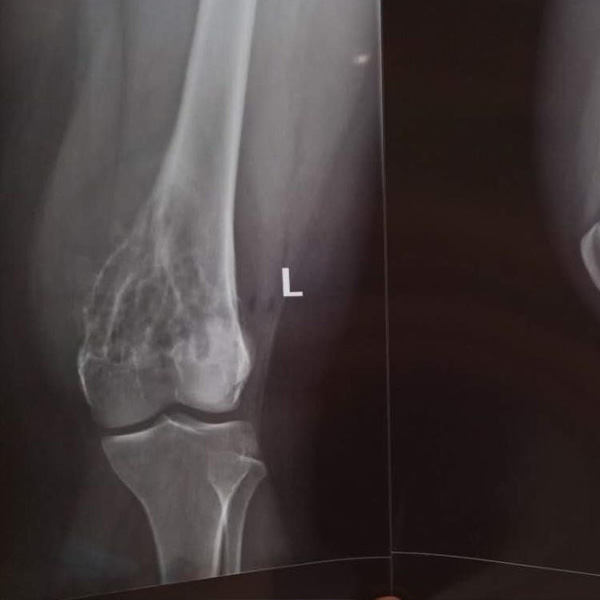

膝關節內翻

患者劉某某,女66歲,左側膝關節嚴重內翻(俗稱的“羅圈腿”),疼痛到不能生活自理。經平臺推薦到哈爾濱醫科大學附屬第二醫院骨關節科就診,......